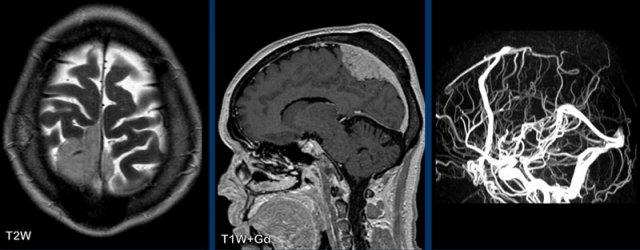

Các hình ảnh này của một bệnh nhân nam 58 tuổi nhập viện với triệu chứng đau đầu ở tư thế ngồi và đứng.

Hình ảnh

Có ngấm thuốc màng cứng đều đặn ở cả khoang trên lều và dưới lều.

Lưu ý các não thất nhỏ.

Tiếp tục với các hình ảnh mặt phẳng đứng dọc…

Hình 1

Các dấu hiệu khá tinh tế, nhưng bao gồm:

- Sa thấp trung não với giảm khoảng cách cầu-vú, xóa bể trên hố yên, dẹt phần trước cầu não và gập góc thân não tại chỗ nối sọ-cổ.

- Vùng dưới đồi gập qua mặt lưng hố yên, tuyến yên hơi phì đại (vòng tròn trắng).

- Liên hợp đồi thị bị hạ thấp; phần sau thể chai bị hạ thấp (dấu hiệu “dương vật rũ”). Lưu ý sự dẹt của bể trên tiểu não.

- Trong trường hợp này, amygdale ở vị trí bình thường và không có thoát vị (vòng tròn vàng).

Kết luận: các dấu hiệu điển hình của hạ áp lực nội sọ.

Hình 2

Sau điều trị bằng miếng vá máu ngoài màng cứng không định vị mục tiêu, não và thân não đã trở về vị trí bình thường với sự bình thường hóa cấu hình các bể và não thất IV.